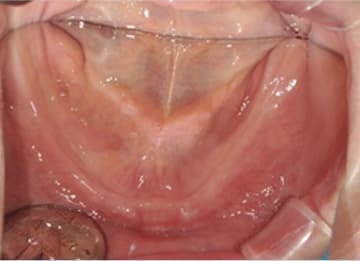

Edentulismo completo

El edentulismo completo es la ausencia total de dientes en una o ambas arcadas.

Los pacientes tienen dificultad para masticar, hablar y pueden sentirse incómodos con su apariencia.

El tratamiento puede incluir la colocación de una prótesis completa sobre implantes, proporcionando una solución fija y estable